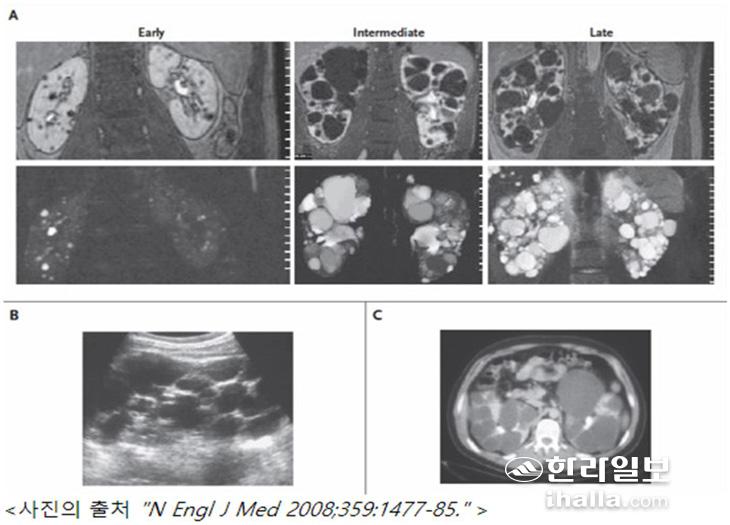

상염색체 우성 다낭성 신증환자의 영상소견(A)MRI scans, (B)ultrasound scan, (C)axial CT scan.

낭종성 신질환 중 유전성을 갖는 질환에서는 대표적으로 상염색체 우성 다낭성 신질환(Autosomal dominant kidney disease,ADPKD)이 있으며 전 세계 최대 1200만명이 진단을 받아 치료받고 있는 가장 흔한 유전성 신장질환이다.

상염색체 우성 다낭성 신질환은 부모 중 1명에서 폴리시스틴(polycystin)이라고 하는 단백질을 만드는 유전자 (PKD 1,2)에 결함이 있는 경우 발병하는 질환으로 상염색체 우성으로 유전돼 세대를 건너뛰지 않고 자녀에게 바로 50%의 확률로 유전된다.

상염색체 우성 다낭성 신질환은 소아에서 발병하는 경우는 드물고, 대부분 성인이 되면 발병하며 보통 20대 이후부터 발생하기 시작하는데, 20대에는 낭종 개수가 적고 크기도 작아 증상을 잘 느끼지 못하는 경우가 많다. 30대 이상부터는 낭종이 커지면서 신장이 커다란 혹으로 만져지거나 좌우 옆구리가 아프고 혈뇨가 나타날 수 있지만, 낭종이 많이 커질 때까지 증상이 없어 검사를 하지 않으면 모르는 경우도 많다.

나이가 들수록 낭종의 개수가 많아지고 크기도 커지면서 고혈압이 대부분 발생하고, 신장 기능을 떨어뜨리게 되며 보통 30대 후반부터 신장기능이 감소하기 시작해 50%는 60대 정도에 신장기능이 10% 이하로 나빠져 투석이나 이식을 받아야하는 경우가 발생하기 시작한다. 따라서 다낭성 신질환의 가족력이 있으면 증상이 없더라도 정기적인 신장 기능 검사와 초음파 검사를 받으면서 관리할 것을 추천한다.